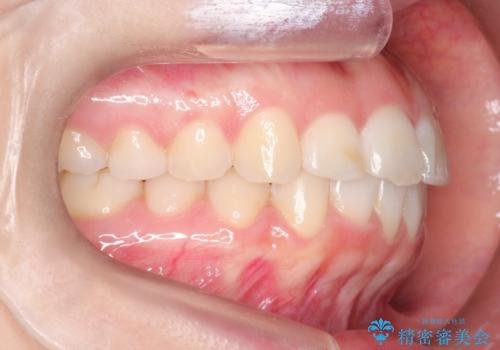

【インビザライン】前歯が出ているのを治したい

- 前歯が出ていることを主訴に来院されました。

前歯の突出感が改善され、満足していただきました。